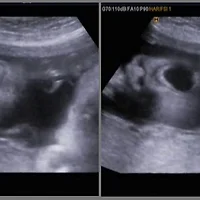

| [34주] 초음파, 역아 ㅠ, 수제초코렛 제작, 중고 천기저귀 (0) | 2015.08.30 |